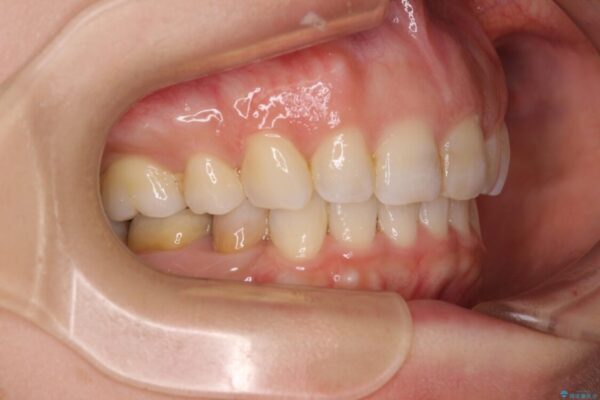

口元の閉じにくさと、奥歯の咬み合わせを気にして来院された患者様です。

左下の大臼歯2本が顕著に舌側に傾斜しているため、まずは奥歯の咬み合わせを改善をし、その後上下左右の第1小臼歯4本を抜歯することで口元を引っ込めながら整えることとしました。

奥歯の咬み合わせ改善には1年ほどの期間と処置中の噛みにくさを強いることとなりましたが、抜歯後はスムーズに治療を完了させることができました。

歯ぎしりの際に奥歯が干渉していた咬み合わせも理想的な状態に改善できました。

治療前

• 【モニター】出っ歯と咬み合わせを改善 ワイヤー装置の抜歯矯正 治療前画像